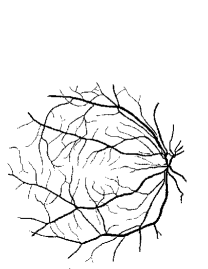

Figure 9: Ground truth (left) and segmentation result (right): (a) and (b) are the images from DRIVE dataset, (c) and (d) are the images from the STARE dataset

V-B Vessel Segmentation Performance

The segmentation performance of the proposed model on three public available datasets is given in Table IV. It can be observed that the proposed model can achieve more than 95%percent9595\% segmentation accuracy on the DRIVE, STARE and CHASE_DB1 datasets, with the highest accuracy score Acc=96.0%𝐴𝑐𝑐percent96.0Acc=96.0\% achieved in the DRIVE dataset. Some exemplary segmentation results are shown in Fig.9. When treating the unknown regions as background regions, AUC=0.833 of trimap is 2.6%percent2.62.6\% lower than the proposed model while Acc of trimap is similar to the proposed model. In addition, Se=0.679𝑆𝑒0.679Se=0.679 of trimap is 5.7%percent5.75.7\% lower than the proposed model. These observations show that trimap can already have good segmentation performance, which indicates that the selection of region features is very effective in segmenting blood vessels. From Table IV, it can be observed that the model with vessel skeleton extraction can achieve more than 5%percent55\% increase of Sensitivity𝑆𝑒𝑛𝑠𝑖𝑡𝑖𝑣𝑖𝑡𝑦Sensitivity and 2%percent22\% increase of AUC𝐴𝑈𝐶AUC compared with the model without vessel skeleton extraction while Acc𝐴𝑐𝑐Acc of the model with vessel skeleton extraction is similar to the model without vessel skeleton extraction, which demonstrates the effectiveness of vessel skeleton extraction.